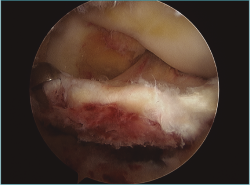

Fractura-avulsión de la eminencia tibial en varón de 14 años. Imagen obtenida durante la exploración artroscópica inicial. Se observa fragmento óseo que incluye la inserción del ligamento cruzado anterior (LCA) en las espinas tibiales.